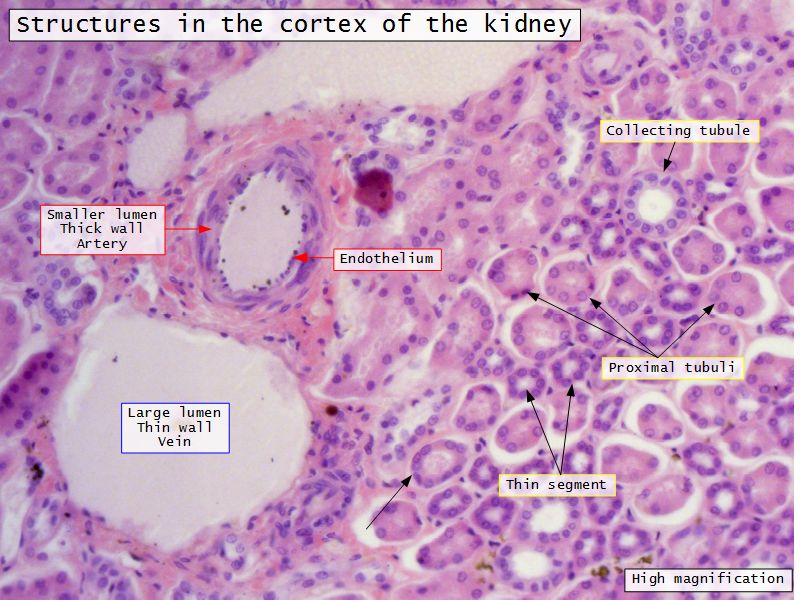

Appearance

- Cortex

- Renal corpuscles

- Convoluted tubules

Kidney lobule

- Group of neprons

- Open into branches

- Same collecting duct

- Not clearly demarcated

- Interlobular arteries/veins

Proximal convoluted segment

- Longest part of nephron

- Wide triangular cell

- Spherical nucleus

- Indistinct cell borders

- Luminal surface

- Striated brush border

Loop of Henle - thin

- Narrow lumen

- Thin wall

- Squamous epithelium

- Looks like capillaries

Collecting tubule

- Cuboidal to columnar epithelium

- Distinct lateral borders